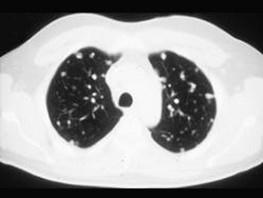

问题 女,72岁,咳嗽,胸闷,呼吸困难1月余,1年前行结肠癌根治术,CT检查如图,请选择最可能的诊断 ( )

选项 A、间质性肺炎 B、粟粒型肺结核 C、肺转移瘤 D、尘肺 E、肺癌

答案 C